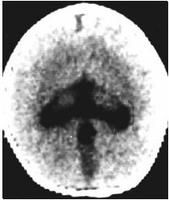

CT和MRI表現依畸形輕重程度而異。1、無腦葉型:無大腦半球,僅有一層菲薄的原始皮質圍繞單一擴大的腦室,第三腦室位於單腦室下方,第四腦室正常。MRI可顯示半球間裂與大腦鐮完全缺如,單側無腦葉常呈盾形,胼胝體缺如,鞍上單腦室馬靴形,第三腦室缺如等。此型最嚴重。

半腦葉型影像3、腦葉型:有明確的側腦室,常擴張,額角頂部扁平或呈方形,丘腦被發育完好的第3腦室分開,透明隔一般缺如,但大腦鐮與胼胝體已部分形成,半球間裂已形成,但殘存的腦葉融合,常見於半球前部及扣帶回處。